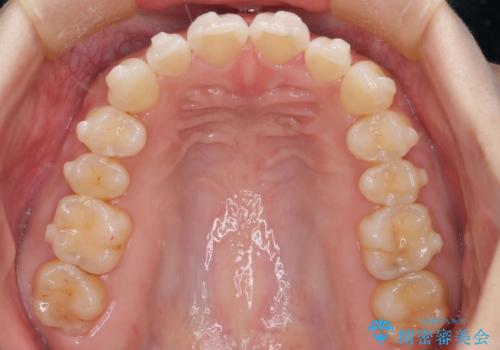

【インビザライン】前歯が出てるのを治したい

- 前歯の凸凹と前突を主訴に来院されました。

インビザラインにて治療をおこない、歯並びを改善することができました。